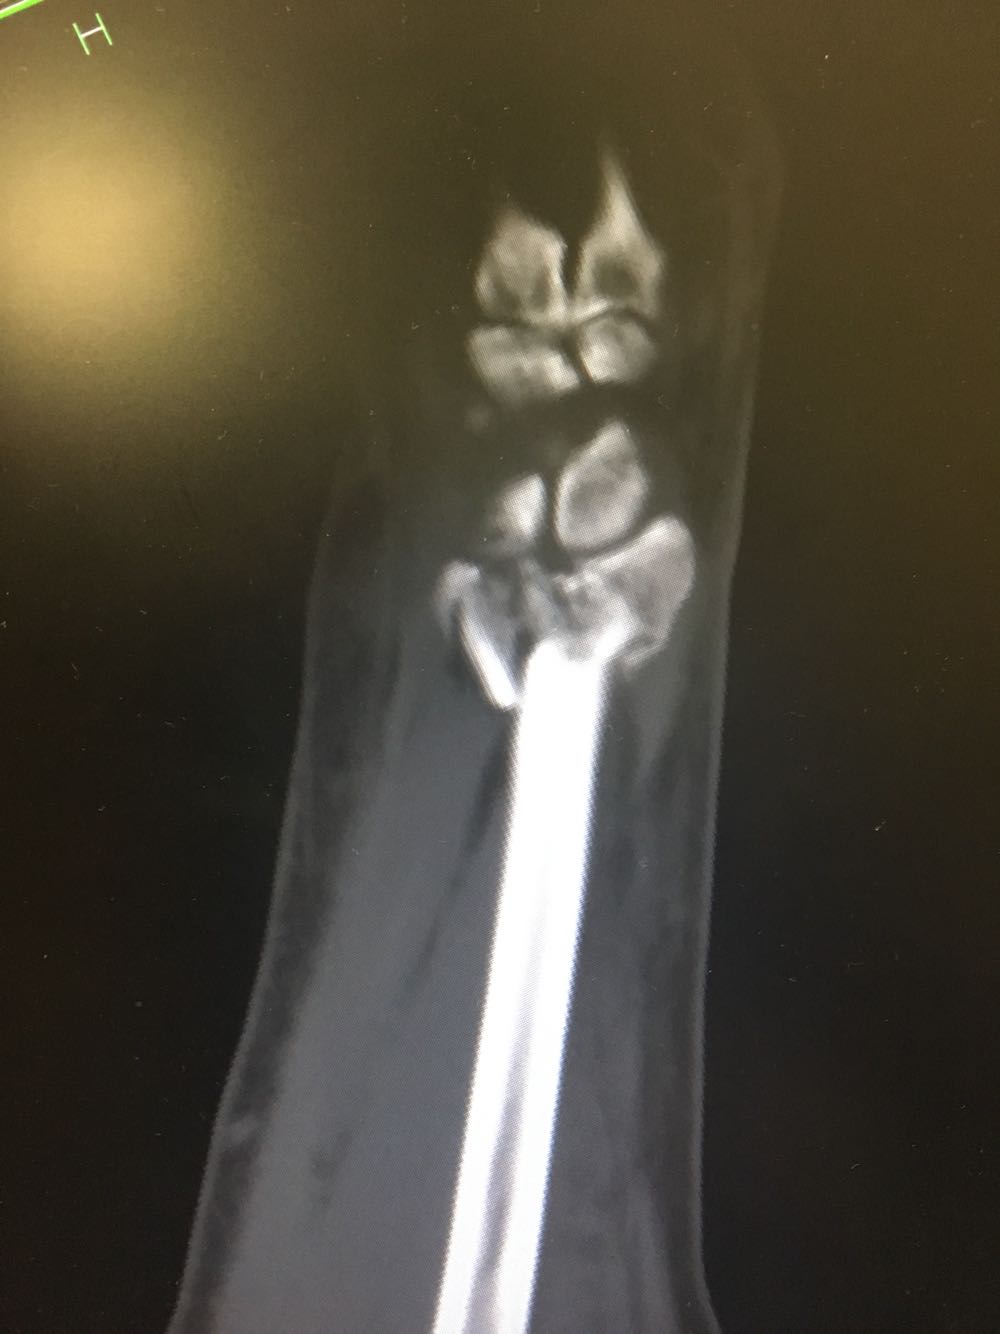

右尺桡骨双骨折

患者,男性,52岁 主诉:摔倒后右腕关节活动受限2天 现病史:患者于2天前于不慎,身体向右摔倒,右手掌着地后突感右侧腕部剧烈疼痛,后出现肿胀伴活动障碍,否认头晕头痛、恶心呕吐等不适,未见淤斑淤点,遂至我院就诊,查X片示:右侧桡骨远端及齿骨茎突骨折,现为进一步诊治收治入院,发病以来,神清,精神可,胃纳夜眠可,二便无殊,体重无明显变化。

查体:右手腕部压痛明显,伴活动受限,其余部位压痛不明显,患侧手指感觉及运动正常。 辅检:腕部CT

诊断:尺桡骨远端骨折(右侧) 治疗:完善术前检查后手术内固定